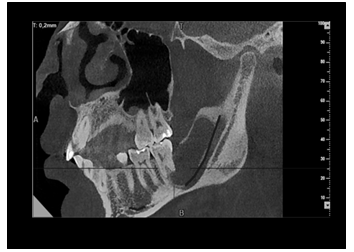

En la Tc Cone Beam en una vista oblicua se visualizó imagen unilocular hipodensa de bordes corticalizados compatible con lesión quística (Figura 3).

Figura 3 Corte de tomografía computarizada de haz cónico, en donde se evidencia en vista oblicua una imagen hipodensa compatible con la lesión, donde se observa desplazamiento del nervio dentario hacia la basal mandibular. Fuente: Historia Clínica. Especialización Cirugía Bucal ULAC-IDOLA. 2022.